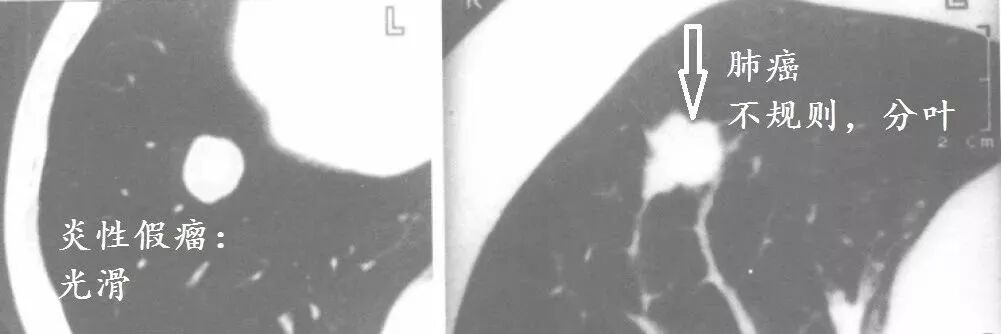

癌,乃魔鬼,张牙舞爪的魔鬼,甚至是吸血鬼。所以,肺癌的CT的特征就是不规则的肿块,有毛刺、分叶,牵拉胸膜引起胸膜凹陷,烂糟糟的空洞,吸血鬼征:血管向肿块聚拢,以供肿瘤吸血。

这么多征象一起存在,肺癌妥妥的,接近100%。

典型肺癌。

看吧,肺癌就是不规矩。